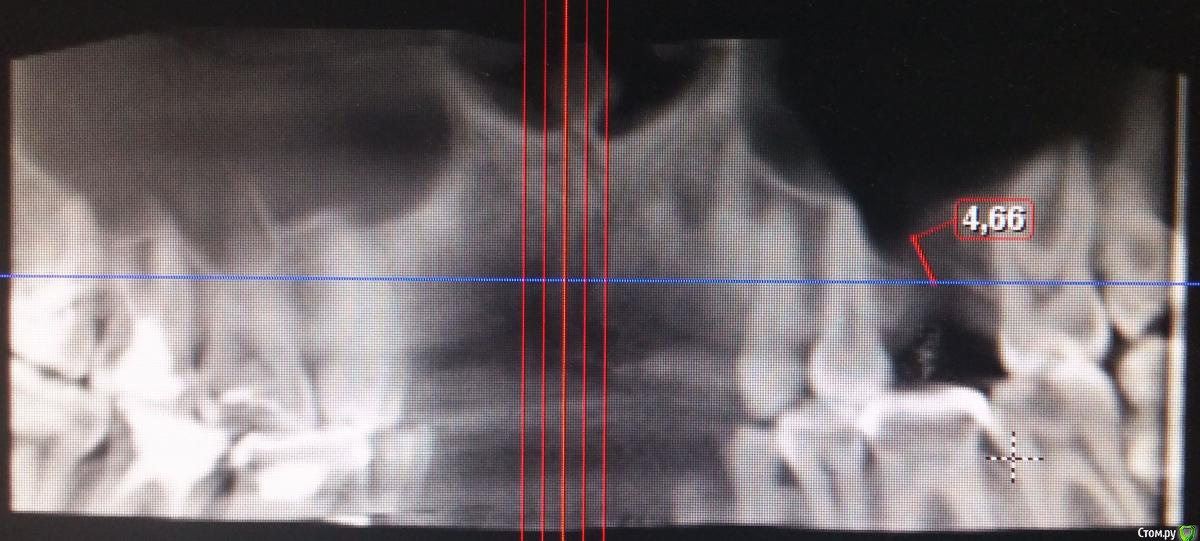

Alejandro Опубликовано 12 июня, 2015 Поделиться Опубликовано 12 июня, 2015 К сожалению, в нашей стране имплантация не является основным методом замещения дефекта зубного ряда, а всего лишь метод выбора. Поэтому постановку мостовидного протеза здесь произвести возможно. Только учитывайте все негативные последствия данной процедуры, в том числе атрофию костной ткани под промывной частью мостовидного протеза (место отсутствующего зуба). Да, и кстати, обрабатывать под коронки здесь прийдётся минимум 3 зуба, чтобы сильно не перегружать. Относительно синуслифтинга. Кроме цены Вас не должно ничего смущать: в умелых руках доктора это рядовая процедура, к которой он всегда готов, даже внепланово.PS А почему высоту альвеоляра померили с середины? 1 Ссылка на комментарий

Yudjin Опубликовано 14 июня, 2015 Автор Поделиться Опубликовано 14 июня, 2015 К сожалению, в нашей стране имплантация не является основным методом замещения дефекта зубного ряда, а всего лишь метод выбора. Поэтому постановку мостовидного протеза здесь произвести возможно. Только учитывайте все негативные последствия данной процедуры, в том числе атрофию костной ткани под промывной частью мостовидного протеза (место отсутствующего зуба). Да, и кстати, обрабатывать под коронки здесь прийдётся минимум 3 зуба, чтобы сильно не перегружать. Относительно синуслифтинга. Кроме цены Вас не должно ничего смущать: в умелых руках доктора это рядовая процедура, к которой он всегда готов, даже внепланово.PS А почему высоту альвеоляра померили с середины?примерно так мерил высоту стоматолог, у него даже еще меньше получилось, примерно 4.55 мм. А какие будут все негативные последствия после установки моста? и что такое атрофия костной ткани? Ссылка на комментарий